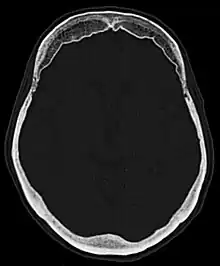

Hyperostosis frontalis at CT

| Hyperostosis frontalis interna in a 74-year-old woman | |